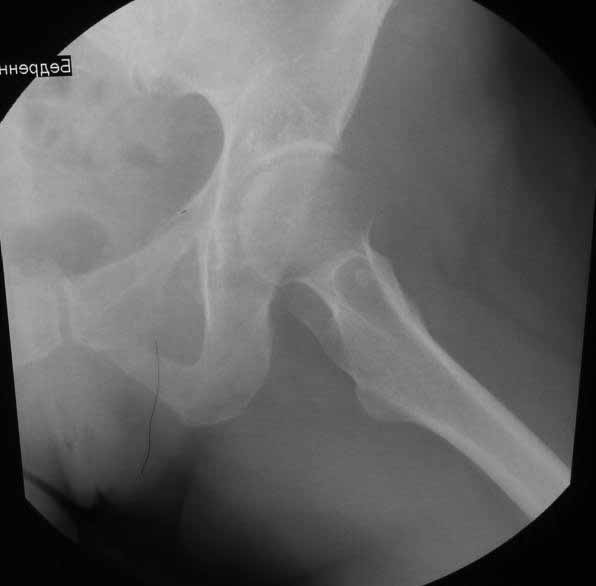

Уважаемые коллеги. Хотелось бы услышать мнения и советы по представляемому случаю. Пациентка 45 лет. Бесцементное эндопротезирование левого тазобедренного сустава 6 лет назад (впадина RM, Mathys, металл-металл, ножка Зульцеровская). За 10 лет до протезирования – коррегирующая остеотомия бедренной кости, которая не срослась в течение года до удаления пластины, а затем срослась в течение 3 месяцев иммобилизации в кокситной повязке. После протезирования получилось наблюдать пациентку почти постоянно, поскольку через 2 года синтезировал ей лодыжки на оперированной стороне, затем, через несколько месяцев удалил фиксаторы, а в 2009г. резецировал мениск на противоположной стороне. Боли все эти годы не беспокоили. Пациентка чуть выше среднего роста, вес тела нормальный. Физические нагрузки переносила хорошо. Работает на 7 этаже без лифта. Год назад экстирпация матки по поводу лейомиомы больших размеров. Несколько месяцев назад появились боли в области левого тазобедренного сустава. При рентгеновском и КТ исследованиях (июль с.г.) – нестабильность тазового компонента. От предложенной замены протеза пациентка на тот момент, слава богу, отказалась. Через какое то время боли в области левого тазобедренного сустава практически полностью прошли, а около 2 месяцев назад появилось ощущение патологической подвижности таза и боли в паху справа, которые через некоторое время уменьшились, а потом снова усилились после значительных физических нагрузок (много ходила по песку на пляже, носила тяжести). Ежедневно принимала диклофенак. На рентгенограммах – переломы правой лонной кости. Сейчас госпитализирована из-за болей в паху справа. Боли слева не беспокоят. На фоне снижения нагрузок в стационаре боли значимо уменьшились. Способна ходить без средств дополнительной опоры.В анализах крови чуть повышены трансаминазы и гамма-ГТ, моча без особенностей.

Вопросы: -правильно ли я расцениваю переломы как стрессовые на фоне неполноценного таза (pelvic insufficiency stress fractures)? -Можно ли так же расценить ситуацию на стороне протеза и, соответственно, не торопиться с ревизией, рассчитывая на вторичную стабилизацию? Уж больно не хочется менять ножку. -Если думать о ревизии, то когда? На представленных снимках тазобедренный сустав до и сразу после операции, затем 2 снимка 2009г., когда ничего не беспокоило, затем КТ 2-х месячной давности и вчерашние рентгенограммы обоих тазобедренных суставов.